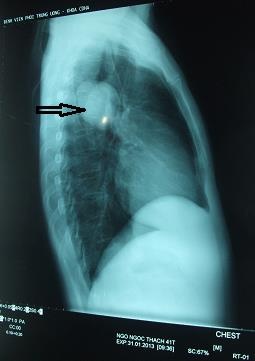

Khi vào ruột non, ấu trùng sẽ chui ra khỏi trứng vào vách ruột, theo máu lên gan, phổi, não, tim, da, cơ, mắt... Tại đây, ấu trùng có thể sống được nhiều tháng, thậm chí nhiều năm. Và vì lạc vật chủ sang người nên chúng không bao giờ phát triển thành giun trưởng thành.

Trẻ em khi mắc thường có biểu hiện sốt nhẹ, ăn ít, gầy yếu, tiêu chảy, buồn nôn, ói mửa; đau cơ và khớp; ho khạc ra đờm có bạch cầu ái toan, khó thở dạng suyễn, thâm nhiễm phổi; da nổi dát đỏ hoặc mề đay, hồng ban đa dạng, gan to, cứng, bề mặt nhẵn, không đau; đôi khi lách hơi to.

Người lớn cũng sốt nhẹ, mệt, nổi mẫn đỏ, ngứa, khó thở dạng suyễn, có thể giảm thị lực một bên do viêm hạt ở võng mạc hoặc viêm nội nhãn mạn tính. Ngoài ra bệnh còn có thể biểu hiện ở khớp, cơ, da, tim hoặc tổn thương thần kinh trung ương do ấu trùng xâm nhiễm vào não, lên cơn động kinh, liệt, co giật, chui vào tủy sống gây rối loạn…